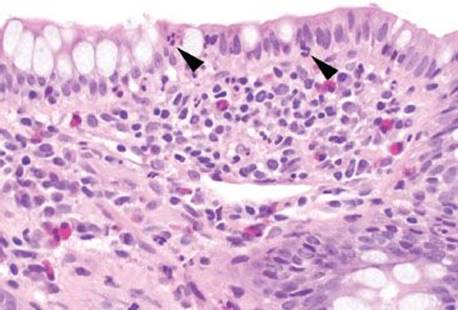

Figure 3.52 Acute ileitis pattern, aphthoid lesion. The diagnosis of acute ileitis implies the absence of chronic injury, as seen in this figure). Although the lymphoid aggregate is gently pushing apart the crypts, there is no chronic injury of the epithelium (note the epithelium could be theoretically peeled off the lymphoid aggregate since the epithelium is not tethered to the lymphoid aggregate by destructive inflammatory injury).

Figure 3.53 Acute ileitis pattern, aphthoid lesion. Higher power of previous case. An aphthoid lesion/ulcer refers to acute inflammation in the epithelium overlying a lymphoid aggregate. In the appropriate clinicopathologic context, an aphthoid lesion can lend support to the diagnosis of Crohn disease.

When assessing the acute ileitis pattern, it is worthwhile to carefully scrutinize the background mucosa for any additional diagnostic clues that might help refine the diagnosis. For example, aphthoid lesions/ulcers consist of acute inflammation in the epithelium overlying lymphoid aggregates and their presence can lend support to a clinicopathologic diagnosis of Crohn disease (Figs. 3.52–3.54). Although granulomata can be difficult to detect in the normally busy-appearing terminal ileum biopsies, their presence can also be helpful when considering the possibility of Crohn disease, infection, sarcoidosis, or medication injury (Figs. 3.58–3.65). Features of chronic mucosal injury are also important to identify, such as pyloric gland metaplasia and architectural distortion, although these features can be seen with chronic injury of any sort, such as chronic NSAID-associated injury or chronic infections (Figs. 3.58–3.73). Histologic features of chronic mucosal injury are extensively discussed in Chronic Colitis, Colon Chapter. Based on the overlapping features between IBD, chronic medication injury, and chronic infection, IBD is remains a clinicopathologic diagnosis that must encompass all available clinicopathologic features (clinical symptomatology, disease course, disease distribution pattern, pertinent microbiologic studies, and family history, etc.).13